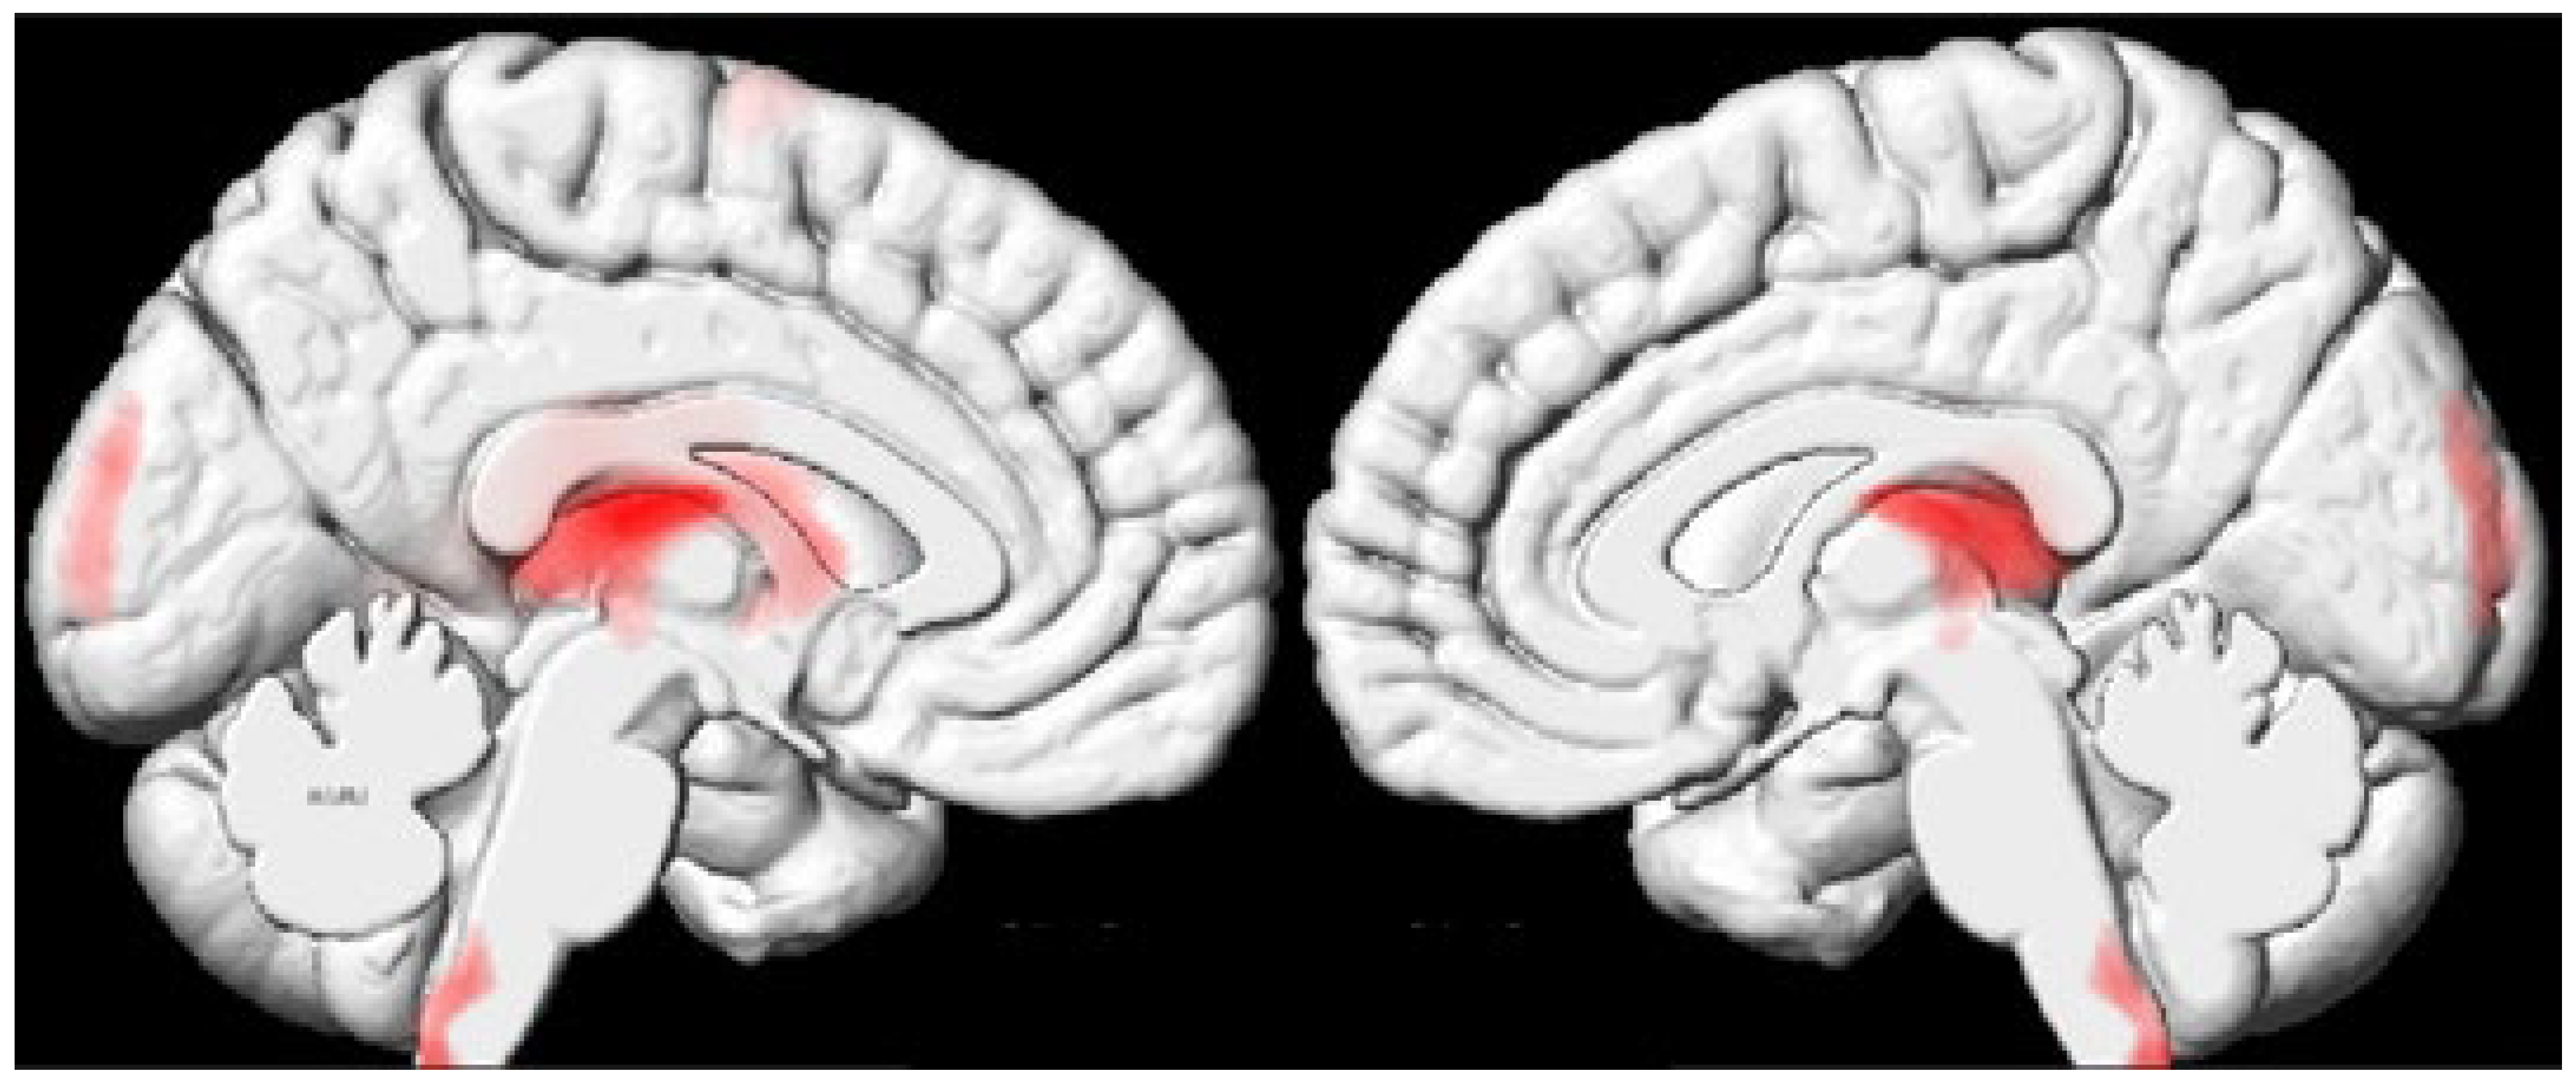

| 2 | −10 | −20 | 14 | −8 | −23 | 12 | 17533 | Thalamus (bilateral) and caudate nucleus (left) |